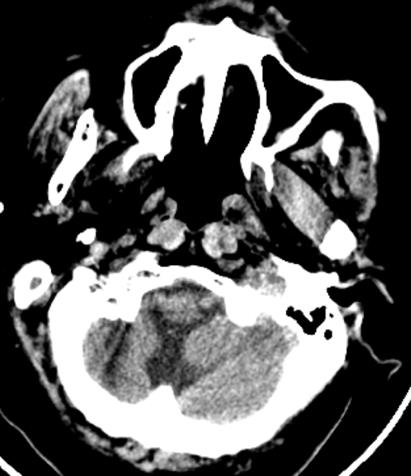

复阅2018年5月9日CT片:左额颞部开颅术后改变,部分颅骨缺如,左颞部脑组织见气体影,双侧额叶及右侧小脑见斑片状高低混杂密度影,大脑镰旁见线状致密阴影,右枕骨骨质断裂。提示左额颞部开颅术后改变,部分颅骨缺如,左颞部脑组织积气,双侧额叶及右侧小脑挫裂伤,蛛网膜下腔出血,右枕骨骨折。

图6-8,2018年5月9日 CT片,左额颞部开颅术后改变,部分颅骨缺如,左颞部脑组织积气,双侧额叶及右侧小脑挫裂伤,蛛网膜下腔出血,右枕骨骨折